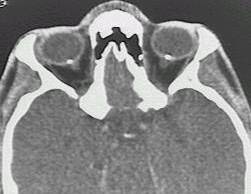

What type of image is it? CT scans or MRI scans (T1 or T2

weighted)

Which plane the image is in? axial, sagittal or coronal.

bony lesion: localized bony expansion (meningioma

and osteoma in which the lesions have the same density as the surrounding

bone; fibrous dysplasia in which the bone density is reduced)? any bony

thinning next to an orbital lesion (suggesting long-standing chronic lesion)?

any lytic lesion (suggesting malignant lesions such as metastasis or myeloma)?

brain lesion (enlarged pituiary fossa suggests

pituitary tumour, wedge-shaped hypodense area suggests cerebral ischamia;

wedge-shaped hypodense area suggests cerebral haemorrahge)?